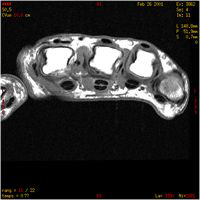

E : Extensor

F : Flexor

Fpl : Flexor pollicis longus

Id : Interossei dorsales

Ip : Interossei palmares

L : Lombricales

M : Metacarpal